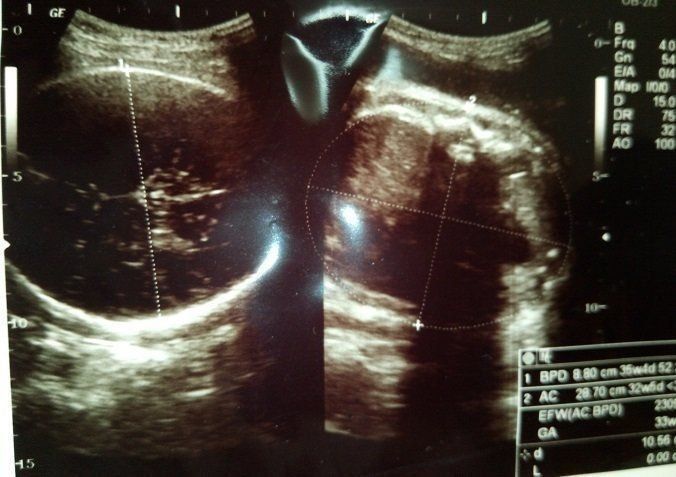

チャーミー小結さんの妊娠35週目のエコー写真

妊娠35週目。低出生体重児とされる2500gを超える時期になってきました。この体重に達すれば管理入院の必要が無くなるので、一旦退院して陣痛が来たらまた分娩に来るか、このまま計画出産するかの選択を迫られました。